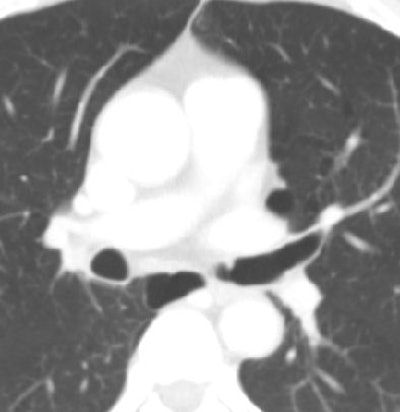

| Axial cardiac CT images in a 63-year-old man with solitary pulmonary nodule visible in full field-of-view only. Above, full-FOV image shows 2-cm spiculated nodule (arrow) in right upper lobe. Below, limited-FOV image obtained at same level shows nodule is collimated from view. This lesion was confirmed to be adenocarcinoma after right upper lobectomy. Images republished with permission of the Radiological Society of North America from Radiology (Vol. 255:2, pp. 369-376). |

"The detection of lung cancer was significantly different between the limited- and full-FOV cardiac scanning examinations, between limited-FOV cardiac scanning and full-FOV thoracic scanning, and between the full-FOV cardiac and thoracic scanning examinations," the authors wrote (p < 0.0001 for all comparisons).

Importantly, of the 26 cancers detected at CT, four (11%) were seen with a limited FOV (covering the heart plus 1-4 cm). Meanwhile, 19 (53%) were seen with a wider FOV that extended from outer rib to outer rib and encompassed the entire lung parenchyma with the portion of the thorax that was imaged. Another 17 cancers (47%) could be detected only in full FOV at thoracic scanning, Kim and colleagues reported.

"Eighty-nine percent of lung cancers would have been missed with limited-FOV cardiac scanning," they wrote. "It is essential that the entire imaging dataset, including the full-FOV images, be evaluated at cardiac CT, because viewing in the limited FOV at cardiac scanning may result in the majority of lung cancers that could be detected on full-FOV images being missed."